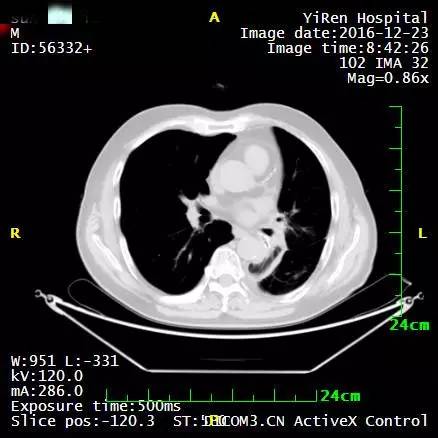

2、患者男性,64岁,小细胞肺癌

2016年3月,王先生因咳嗽加重就诊于当地医院,支气管镜病理检查提示:斟酌小细胞癌的可能性大。

化疗一周期,病情无改善症状加重。

2016年4月,王先生接受了A45治疗,一个月后复查,病灶明显缩小,2016年7月复查,病灶进一步缩小,由于A45治疗具有明显的远观效应,能够激发自身的免疫系统,长期有效的消灭体内肿瘤,2016年12月,王先生肺部病灶几乎全部消失。

治疗前

治疗后

治疗后两个月

治疗后7个月

目前王先生状态良好,没有任何复发迹象。